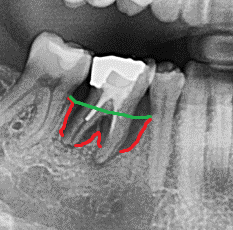

Hier sieht man das Problem:

Zerstörter Zahnhalteapparat – Die erste Abbildung zeigt einen Backenzahn mit einem ausgeprägten Knocheneinbruch. In der zweiten Abbildung ist der Knochenverlauf zum besseren Verständnis noch einmal durch eine rote Linie dargestellt. Die grüne Linie stellt den normalen Knochenverlauf im gesunden Zustand dar. Die Fläche zwischen beiden Linien entspricht dem Knochenverlust. Ursache für dieses Problem ist eine bakterielle Entzündung, die sogenannte Parodontitis. Diese kann den Zahnhalteapparat zerstören und führt unbehandelt letztendlich zum Zahnverlust.